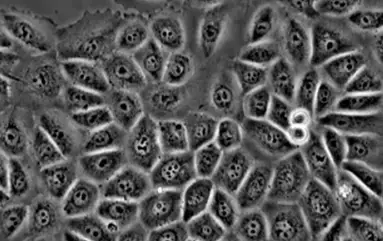

Healthy cell structure under a microscope at multiple magnification

Connective tissue cells before exposure to electrosmog.